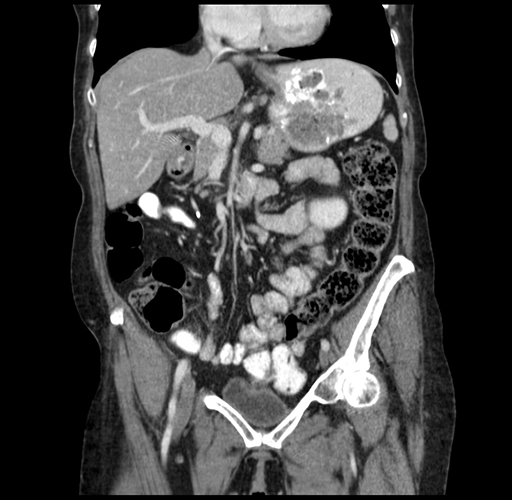

Coronal Venous